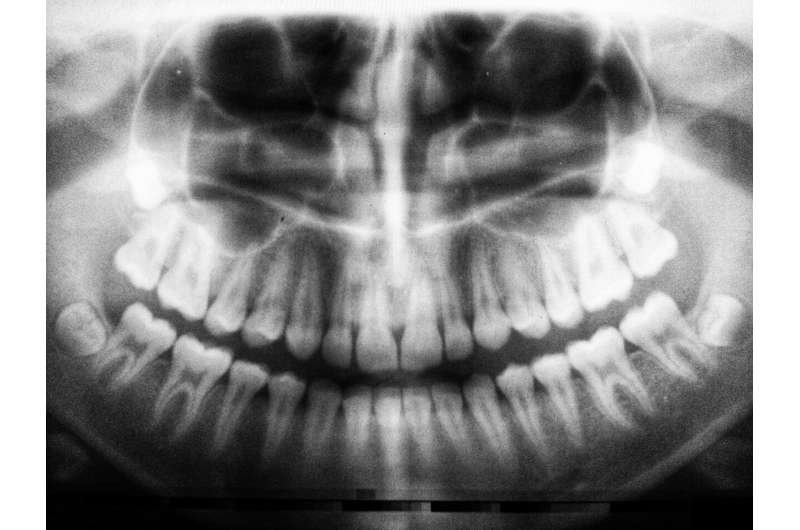

Los pacientes del análisis metabólico presentaban periodontitis apical , una infección profunda alrededor de la punta de la raíz dental. A menudo no causa dolor, por lo que muchas personas no saben que la tienen hasta que se detecta en una radiografía.

En este caso, es la diabetes la que aumenta el riesgo de una cicatrización lenta, no al revés. Un nivel alto de azúcar en sangre debilita la respuesta inmunitaria e interrumpe la reparación ósea, por lo que las lesiones en la punta de la raíz (que se observan en las radiografías como zonas más oscuras donde el hueso no ha cicatrizado correctamente) son más comunes.